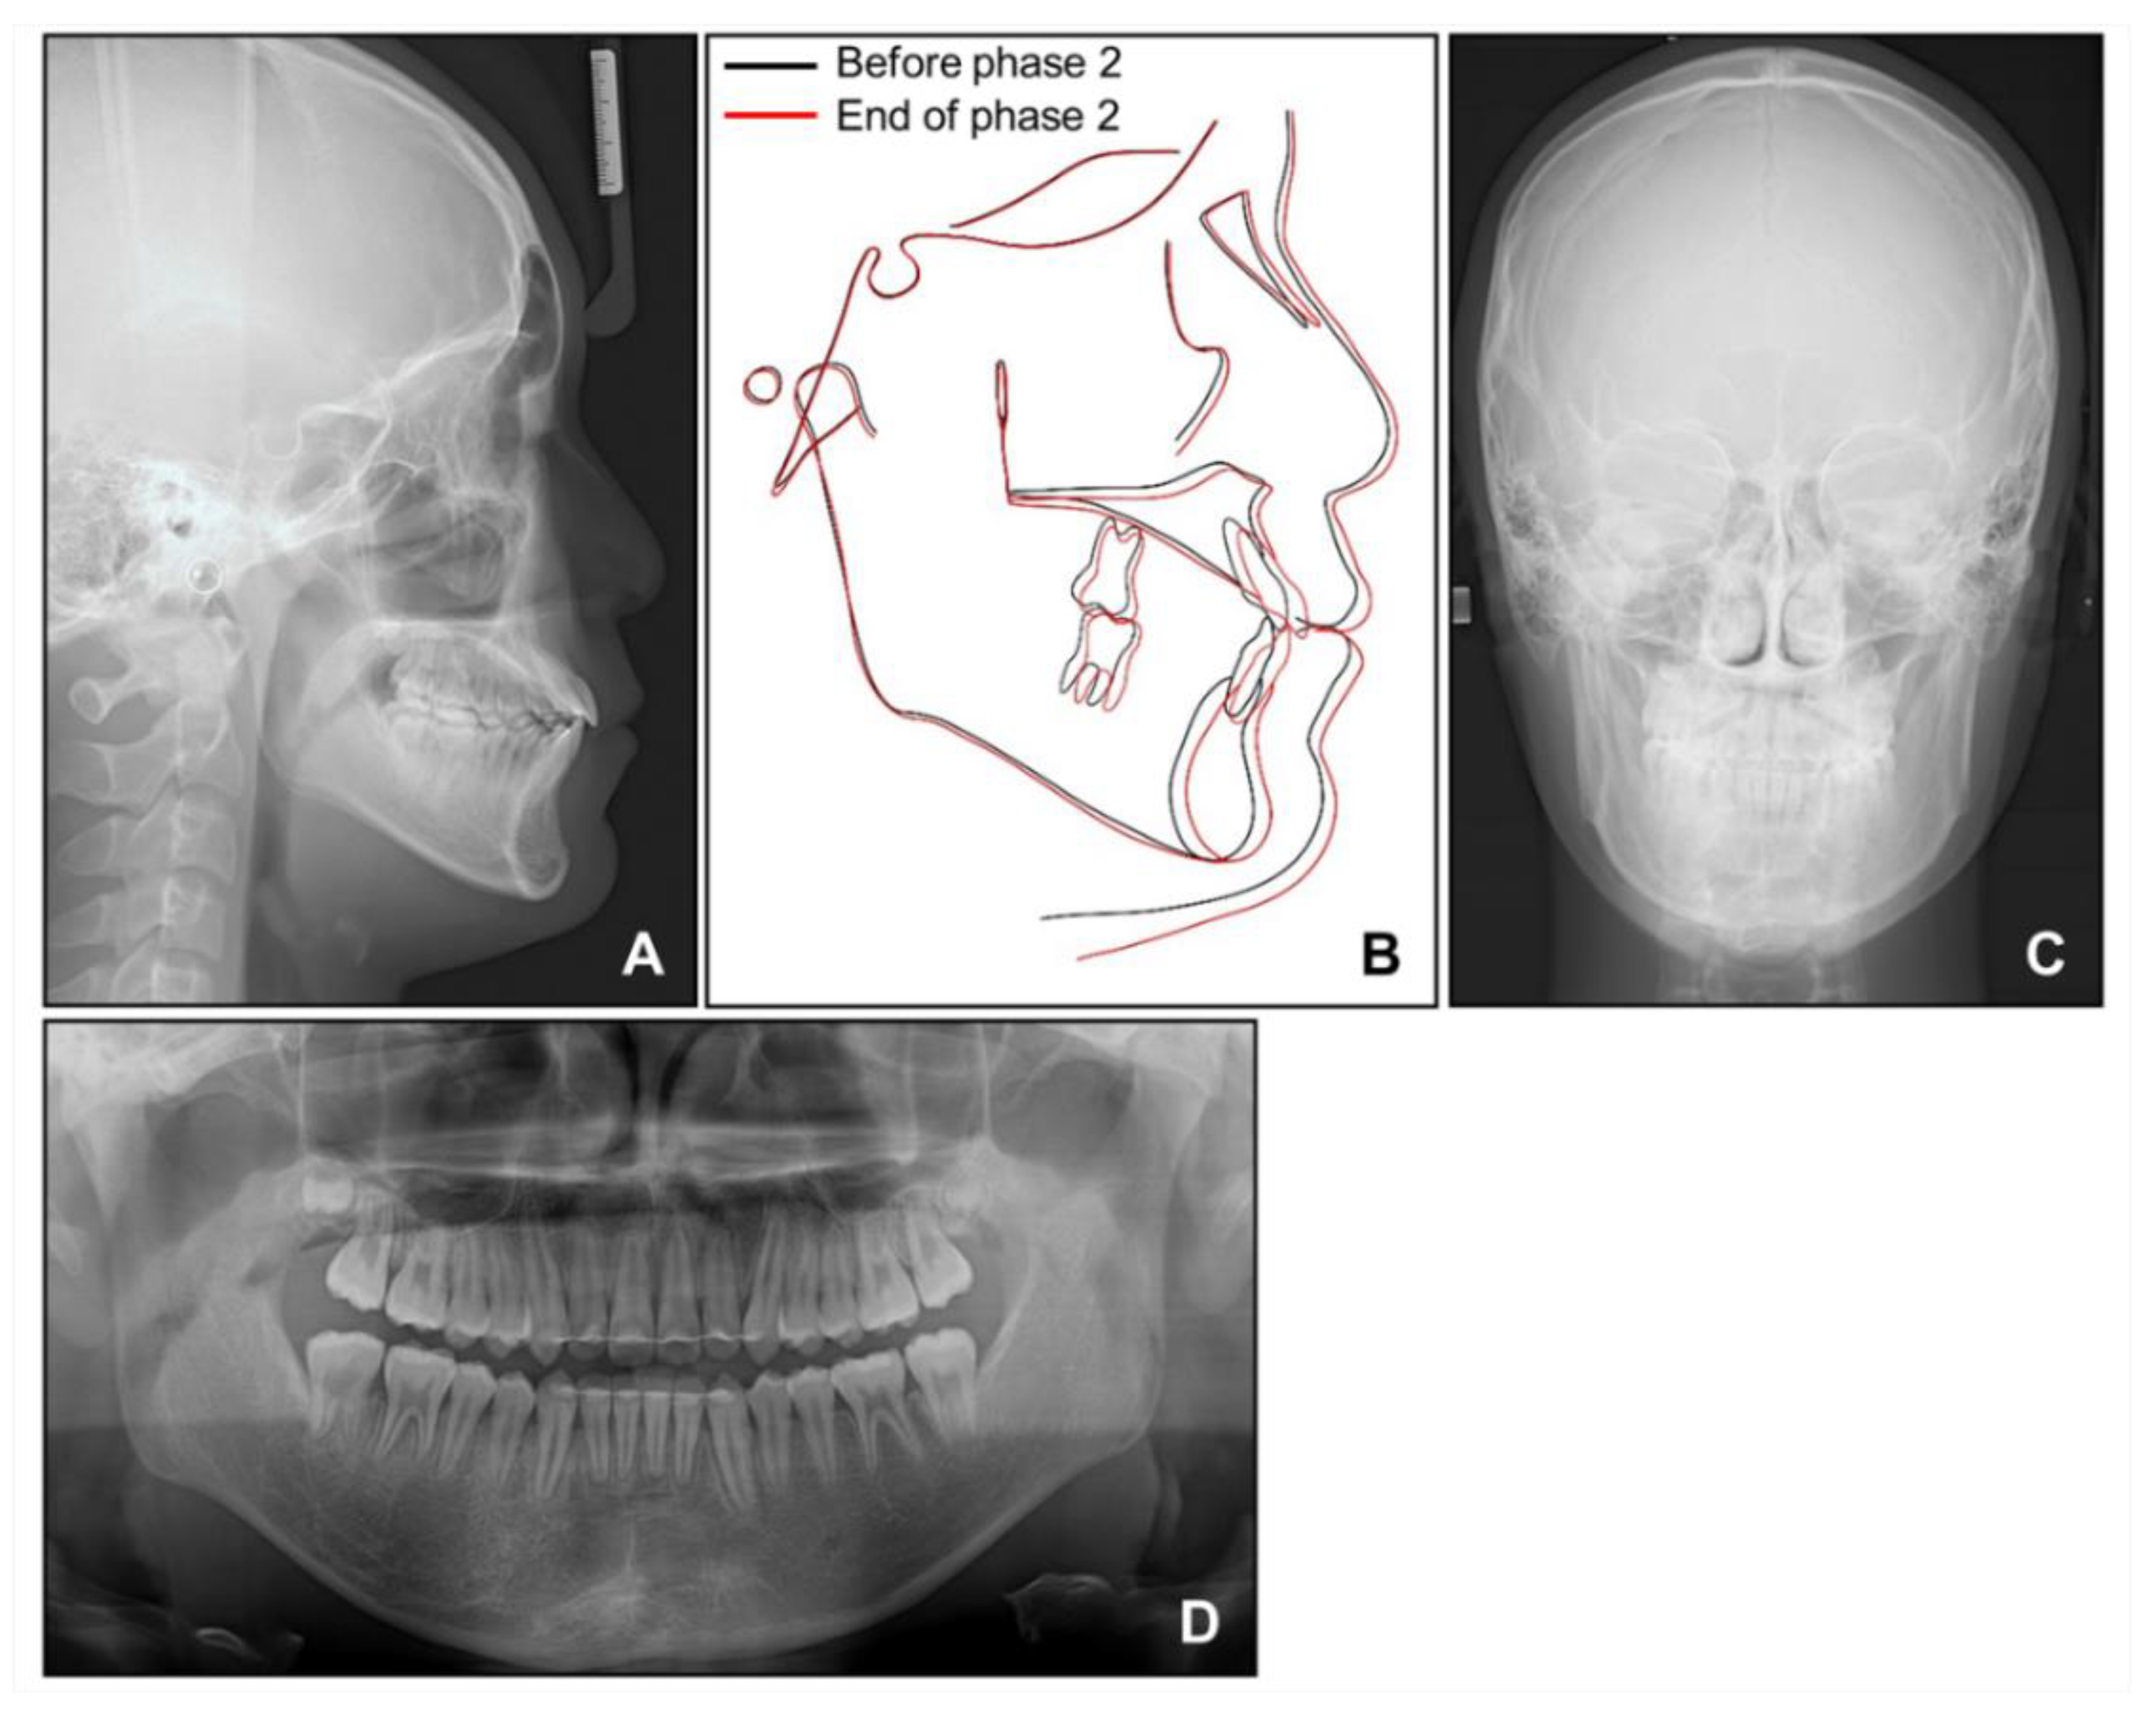

The appliances were removed after 19 months of phase 2 treatment. Fixed retainers were bonded to the lingual surfaces of anterior teeth in both arches. The maxillary and mandibular circumferential retainers were delivered with the anterior bite plate added to the maxillary retainers to prevent the relapse of the deep bite. We instructed the patient to wear them for 24 h a day for the next 6 months.

3. Results

Post-treatment photographs showed that the facial profile was improved, and ideal alignment and occlusion were achieved with a proper overjet and overbite (Figure 10, Figure 11 and Figure 12). The mandibular dental midline coincided with the maxillary dental midline and the facial midline. The canting of the mandibular anterior teeth was corrected with the intrusion of the mandibular right anterior teeth without a loss of periodontal support or root resorption. Although both the nevus and lip canting remained, the darkness of the hyperpigmentation was lightened by periodic laser treatment at a dermatology clinic.

Cephalometric analysis showed that a skeletal Class I relationship was well-maintained after the phase 1 treatment, with an ANB of 2.5°. Both previously lingually inclined maxillary and mandibular incisors were improved to the normal range. The patient was satisfied with the results and remained stable for 1 year after debonding. While a slight relapse pattern of open bite was observed in the left anterior region, no remarkable increase in the right mandibular right hypertrophic region was observed (Figure 13 and Figure 14).

Figure 12. Post-treatment radiographs: (A) Lateral cephalogram; (B) Superimposition before and after phase 2 treatment; (C) Posteroanterior cephalogram; (D) Panoramic radiograph.